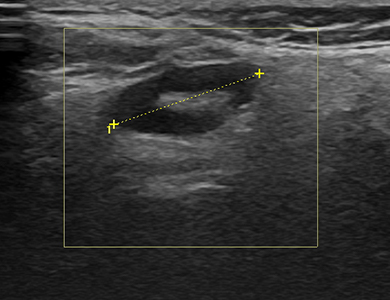

¿ìÃø ÀÌÇϼ± ºÎÁ¾, º¼°Å¸®

img

Á¶Á÷ »ý°Ë¿ë±â±¸(Gun-Biopsy)